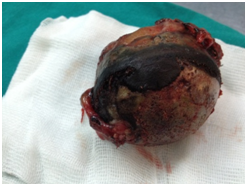

The patient was scheduled for surgery of total right knee arthroplasty. During the surgical approach of the knee we observed the dark pigmentation of the synovium, the bone cartilage, the quadriceps tendon and the menisci. This rare condition, characterized by many as ‘’Black Bone Disease’’, is accompanied by extensive destruction of the femoral condyles and the tibial Plateau due to arthritis. We performed a cemented total arthroplasty and sent pieces of the bones and the meniscus for histological examination (Figure 4).

Histological examination confirmed the clinical diagnosis. The disease is ochronotic arthropathy or alcaptonuria. The confirmation was enhanced by urine examination as well as by examination of pieces of the synovium, the meniscus and bone pieces of the knee (Figure 5) and synovial liquid (Figure 6). At the overview of the patient we detected dark pigmentation of sclera, which is characteristic of alcaptonuria (Figure 7).